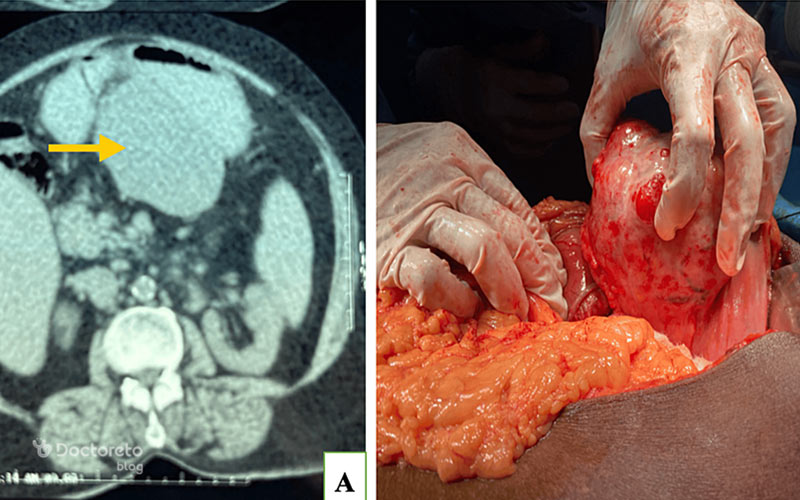

عکس تصویربرداری های سرطان معده خوش خیم

تصویربرداری پزشکی مانند سیتیاسکن و MRI به پزشکان کمک میکنند تا موقعیت، اندازه و ماهیت تومورهای معده را بررسی کنند. در ث تومورهای خوشخیم نیز این روشها کاربرد دارند تا احتمال نفوذ به بافتهای مجاور یا تبدیل احتمالی به بدخیم بیشتر و با دقت بالاتر ارزیابی شود. عکس این بخش نمونهای از این نوع تصویربرداریها را نشان میدهد.

عکس سی تی اسکن سرطان معده خوش خیم

سیتیاسکن ابزار قوی دیگری برای ارزیابی تومورهای معده است. این روش تصویربرداری به ویژه در تشخیص اندازه، موقعیت و ارتباط آنها با ساختارهای اطراف کاربرد دارد. حتی برای سلولهای خوشخیم سرطانی هم سیتیاسکن اطلاعات ارزشمندی در مورد چگونگی رشد و وضعیت بیمار ارائه میدهد. استفاده از این تصاویر کمک میکند تا پزشک نگاهی دقیقتر به تومور معده داشته باشد.